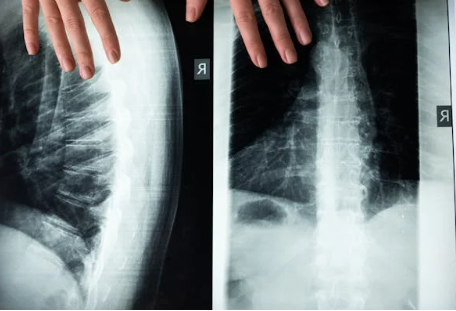

척추측만증은 척추가 옆으로 비정상적으로 휘어진 상태를 말합니다. 정상적인 척추는 S자 형태로 약간 휘어져 있지만, 측만증 환자의 경우 척추가 C 또는 S자 형태로 심하게 휘어져 있습니다.

척추가 옆으로 굽은 각도가 10도 이상 되면 진단한다

척추측만증은 신체 검사, 엑스레이, MRI 검사를 통해 진단됩니다.

- 엑스레이: 엑스레이는 척추의 측만증 정도를 정확하게 보여줍니다.